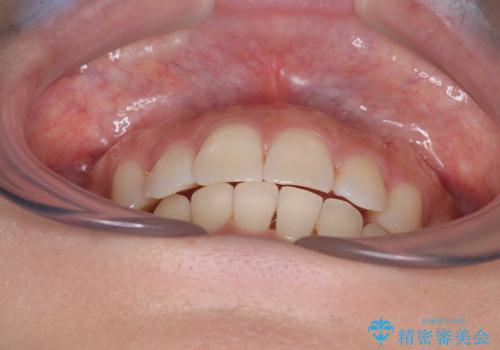

目立つ八重歯を改善 ワイヤー装置での抜歯矯正

上顎の正中位置をほぼ保った状態で、綺麗に仕上げることができました。